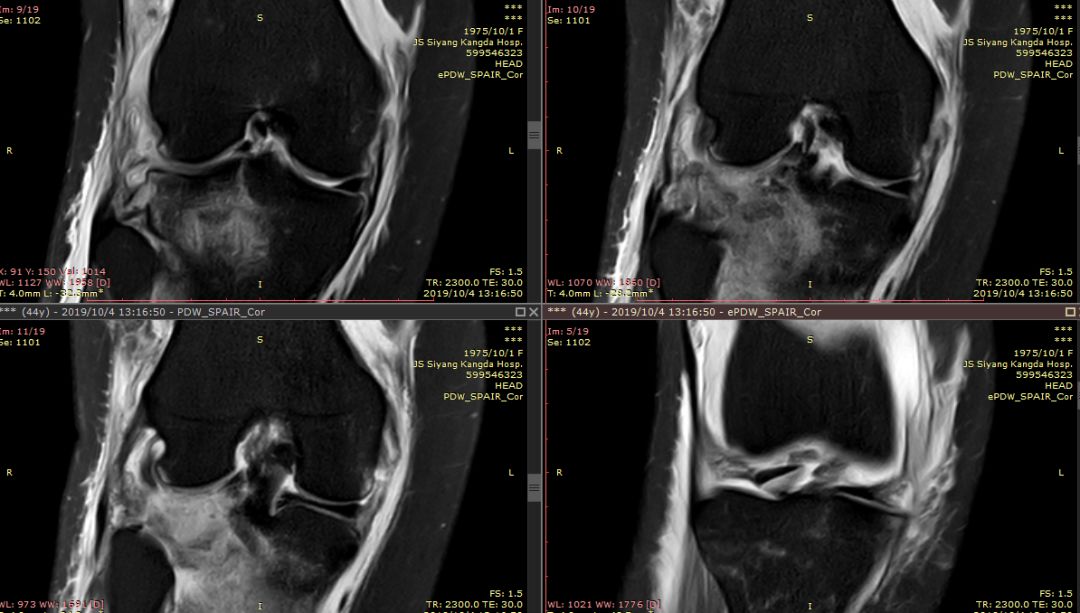

ACL损伤的间接征象:指ACL断裂后胫骨前移位出现的一系列改变。间接征象只能考虑可能有ACL损伤。

1.关节失稳,ACL撕裂,胫骨就相对于股骨前移。

有时前交叉韧带损伤或撕裂,须与半月板撕裂相鉴别,如下例

箭头是撕裂的内侧半月板,前交叉韧带冠状面是连续的,下端胫骨附着处小片绪状高信号影,提示损伤或部分撕裂。